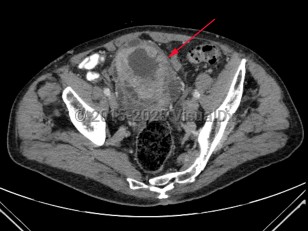

Bladder cancer

Patients with bladder cancer typically present with painless gross or microscopic hematuria, although dysuria, frequency, and urgency may be the presenting symptoms. Diagnosis may be delayed due to the similarity of these symptoms to benign conditions such as urinary tract infections, nephrolithiasis, cystitis, or prostatitis. Urothelial cancer may mimic bladder cancer. In patients younger than 50 years, asymptomatic microscopic hematuria is rarely associated with bladder cancer.

Treatment options depend on depth of tumor invasion and presence or absence of metastatic disease. Transurethral resection of bladder tumor (TURBT) may be combined with adjuvant chemotherapy for early-stage disease with radical cystectomy and/or chemotherapy in late-stage disease.